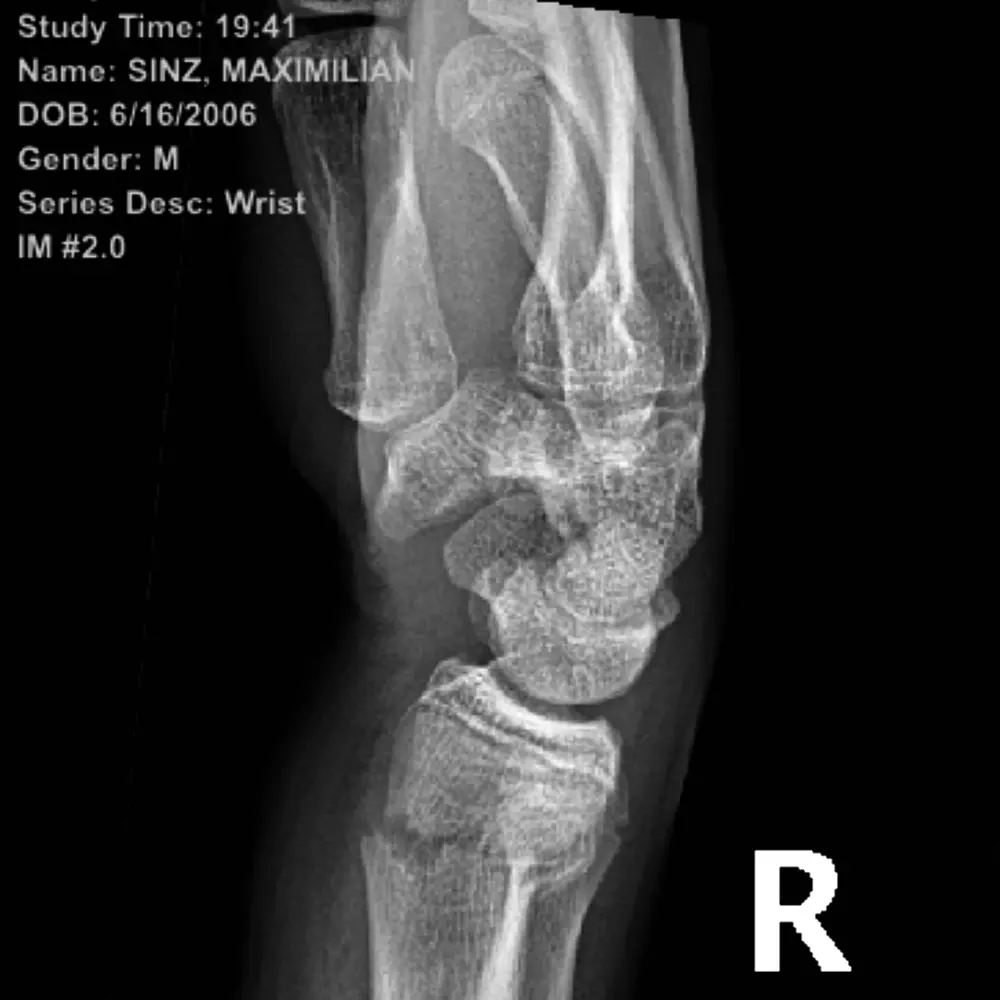

Werden einzelne schmerzhafte Körperteile geröntgt oder im Kernspin dargestellt, bekommen Sie eine Vielzahl von Befunden über Ihre abgenutzten Strukturen und Verschleißteile.

Oftmals bekommen meine Patienten es mit der Angst zu tun, wenn sie von anderen Ärzten erfahren, was alles "altersentsprechend" kaputt ist. Das Resultat dieser heutzutage standardmäßigen Apparatediagnostik führt entweder gleich zur OP-Indikation oder zur ernüchternden Empfehlung: Da kann man eh nichts mehr machen in Ihrem Alter.

Das Ziel ist es, Sie als Mensch zu behandeln und nicht Ihr Röntgenbild.